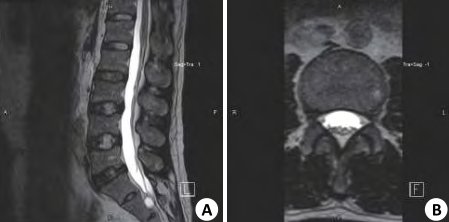

図3:腰椎分離症mri 初期 骨の白い部分が多く重症例だが初期。治癒が十分見込める像。 図4:腰椎分離症mri 軽症例 白い部分が少なく、進行期と判断された例。 ※mriでの腰椎。図3が腰椎分離症重度例。骨の白い部分が濃く出ている。 ②腰椎分離症の診断は、単純x線検査・mri検査・ct検査にて行われる。 ③腰椎分離症の治療は、安静と硬性体幹装具の着用が基本。 ④腰椎分離症のリハビリテーションは腰椎へのストレス軽減を目的に行う。 腰椎分離症とは? 小田菜南子 VICTORYクリニック第二回「子どもと膝」:MRI検査で中学世代の約6割が腰椎分離症の初期段階の兆候も! 競技人生の長さは幼少期が影響。 「止める」勇気で子どもの体を守れ すべての運動の土台となる膝の関節を守る方法について、関節

腰椎分離症 7(ct画像) 初診時 早期に見つかった分離症。 ctでは、まだ分離かどうかはっきりしません。 同左 2カ月後(ct画像) 腰痛がとれたので、すぐに運動を始めてしまいました。 分離の骨折線が分離症発生の病態を把握するため、超初期・初期分離症患者28名(男性25名、女性3名、平均年齢は141歳 )のMRI初診時 MRIのSTIR像を参考に、高輝度変化 (HSC High Signal Change)の広がりを解析したので報告する。Fig 5 初期分離症の sagittal reconstruction CT 画像 分離症は常に pars 尾側から発症する Case 1 Case 2 Case 3 Fig 7 発育期分離症の CT での病期分類 hair line clear gap pseudoarthrosis Early Progressive Terminal direction of maximum principal L5 +1285e+02 S, Max Principal (Avg 75%) +8000e+01 +7